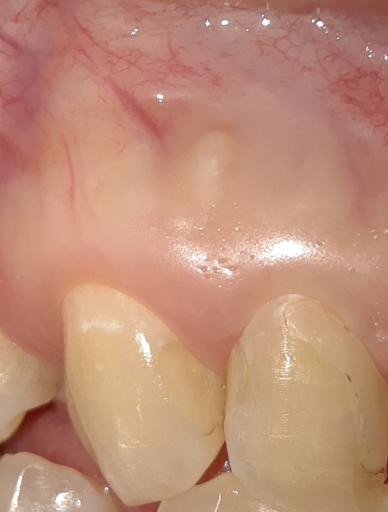

Damaged inferior alveolar nerve during root canal

I had a root canal on a lower molar, not quite a week ago. I had broken the tooth upon chewing two days before, they did xrays and I was told I needed a root canal. I was in the chair for 6 hours, I was told due to the fact that my roots on this tooth curved and care had to be taken to get it all and not break the drill off. I also have very bad pressure hives, so two hours into the procedure my lower jaw,face, started swelling. I didn't think too much about his because of the hives and the assistant was pulling pinching the cheek/mouth out the the way. I have a super tiny mouth and this has alway been a problem with dentist, they used an extra small childs dental block to keep my mouth open. After 6 hours of being in the chair, I told them I had had enough for the day, my face was very swollen, and the dentist hadn't even put the temporary crown on yet but I told him I would be back the next day. After the novicain started wearing off which took hours, I still couldn't feel my lower left lip or my chin. I canceled my appoint for the next day and just thought the numbness was from the pressure hive. The next day I called the dentist and told him that I was still numb and they told me to come in the next day. He told me that it was the alveolar nerve and did a pan scan which I guess they have a "non digital" scanner, which basically told them nothing. He said that I need to go to an oral surgeon to have them assess the nerve. I also have a large lump where the hive was, it was painful but I think its gradually getting smaller, I am concerned about that but more concerned with the nerve. Will this nerve and feel come back? Is this a common occurance? The dentist said he never has heard of this happening except in the case of wisdom teeth extractions. I should also add that the gum between the premolar and first molar is numb as well. Not sure this is the first molar since I had so many pulled when I was younger and getting braces on. I think this must be my second molar in reality. I am very scared that this is going to be permanent. I have terrible dental phobia as it is but this is putting me over the edge. I would appreciate any help you can give me. Is there anything that I could do to help the nerve, i.e. massage, vitamins, etc.? Thank you so much for your time! Susan